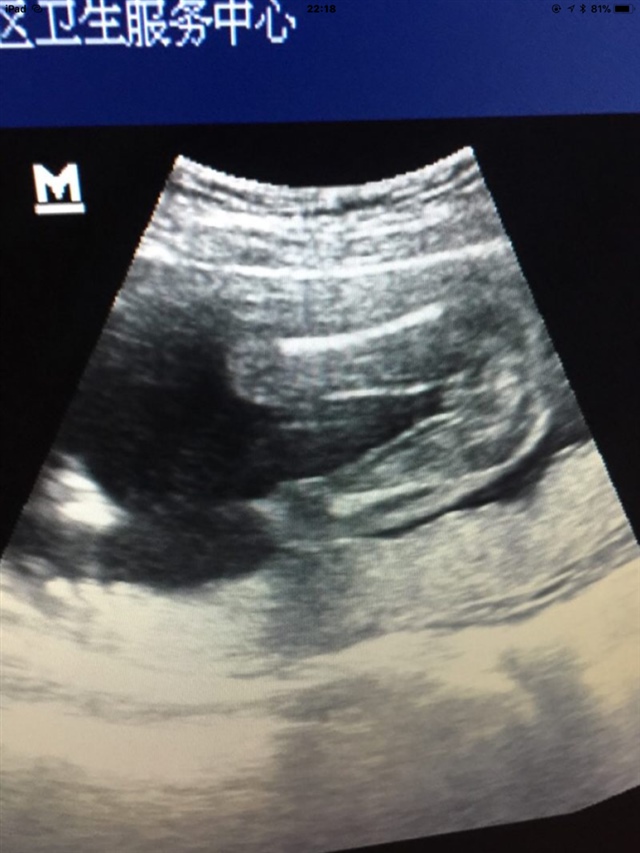

好像是女宝宝

看哪儿看哪儿呀,我怎么不会看这东西呢

***[帖主]:裆部,三条线就是女宝

很明显是女宝宝

***[帖主]:哈哈,我看着也挺明显,又怕是脐带挡着了

大腿和屁股

三条线的话就是女宝宝

黑白b超?

***[帖主]:嗯嗯,我直接照的屏幕

***[帖主]:彩超呀,